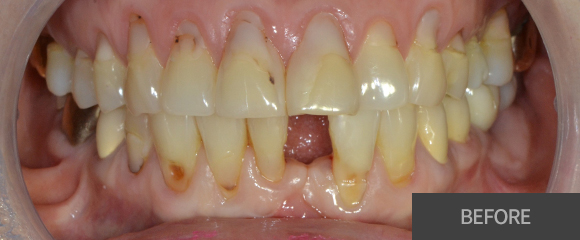

잇몸치료

잇몸치료가 전공 분야인 치주과 원장님께서

꼼꼼하고 꾸준하게 잇몸을 관리해드리고 있습니다.

대학병원에서 주로 시행하는 잇몸 수술까지도 가능한

전문의 원장님과 꾸준한 잇몸관리를 받으시길

바랍니다.